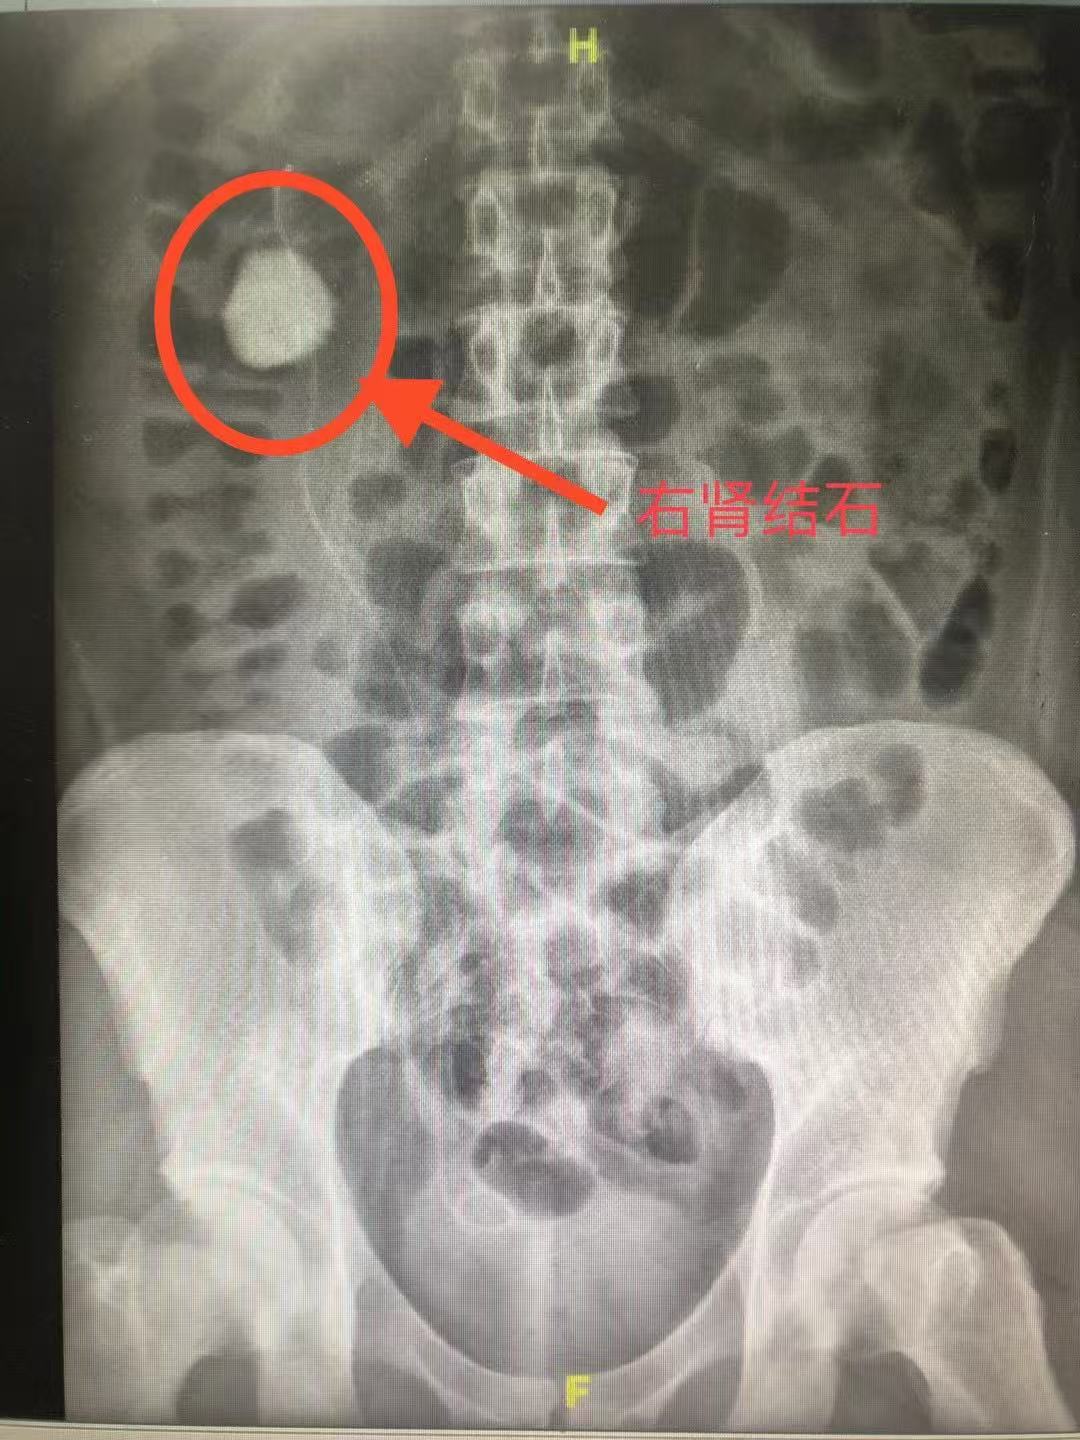

患者张先生(化名)因反复腰痛来院就诊,经CT检查发现左肾盂内存在一枚直径约4cm的鹿角形结石,同时合并轻度肾积水。传统治疗方案多需采用经皮肾镜取石术(PCNL),但存在出血风险高、恢复周期长等问题。经泌尿外科团队综合评估,结合患者对微创治疗的诉求,最终决定采用输尿管软镜钬激光碎石术。